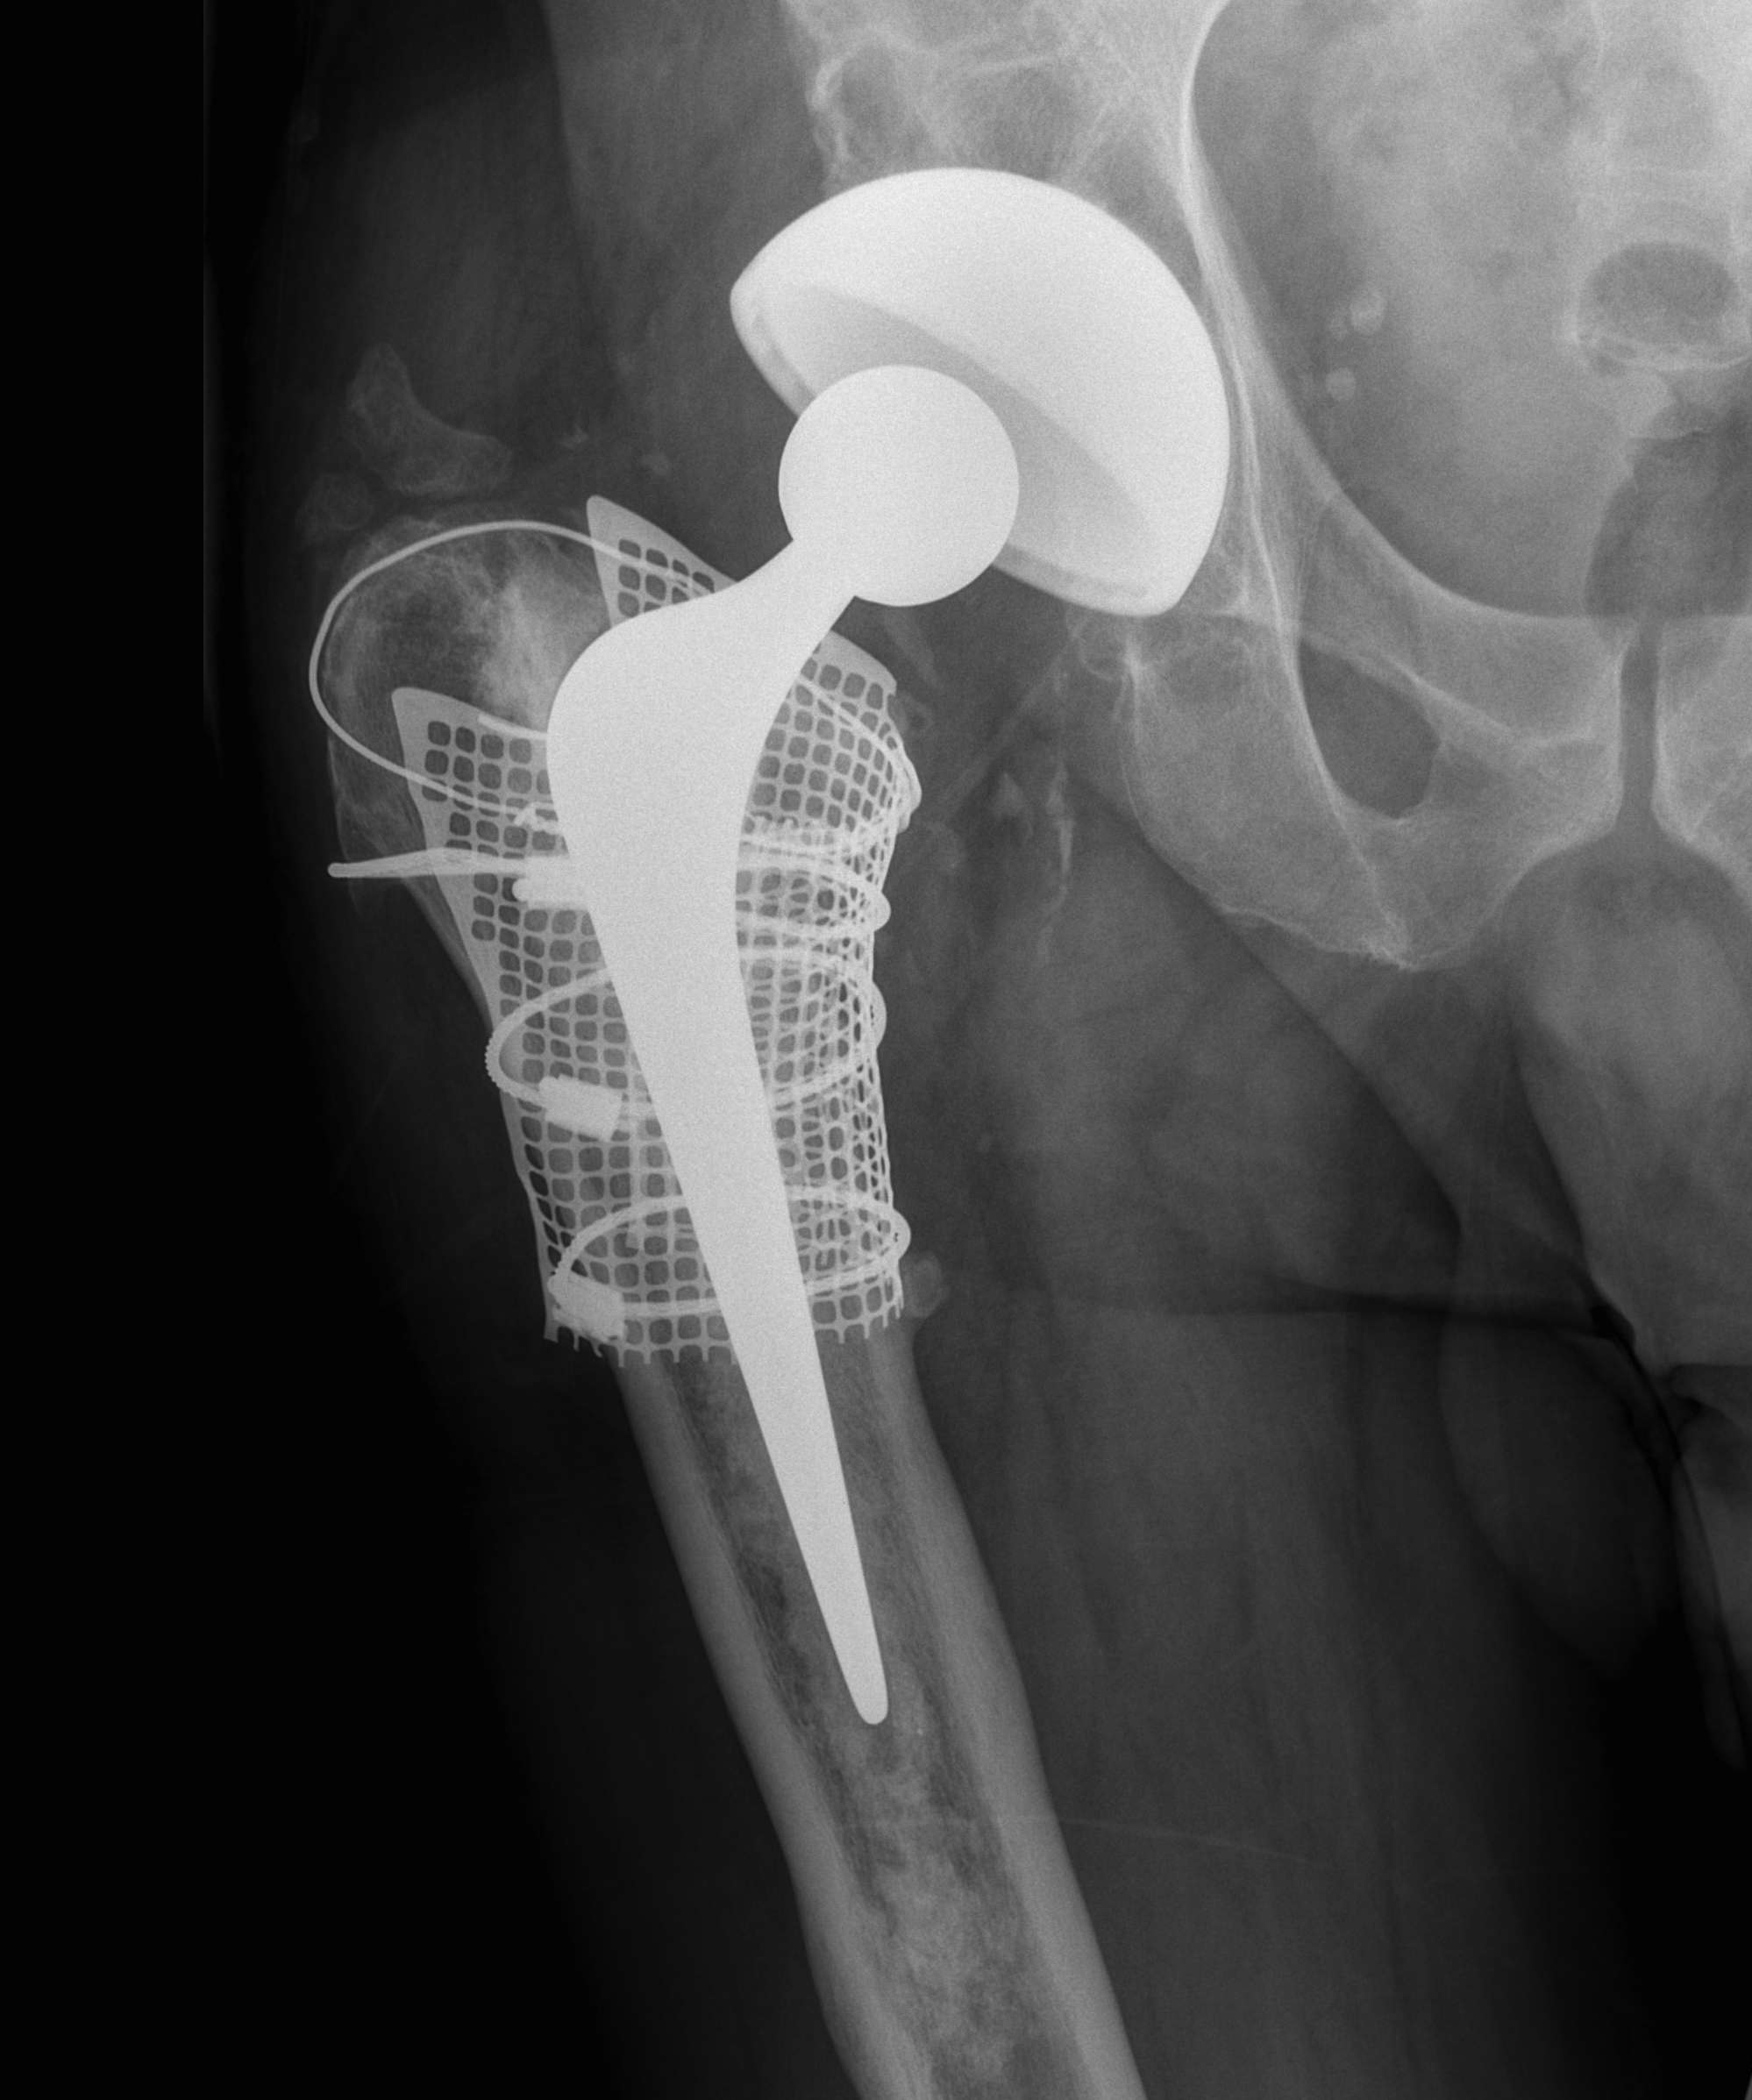

D. Bulk Structural Proximal Femoral Allograft

Indications

- proximal defect > 3 cm

Technique

- desired stem cemented into allograft

- press fit distally into host femur

- step cut graft host junction

- secure cerclage wire and onlay cortical strut

- proximal host bone wrapped around allograft with ABD preservation

- very important – abductor mechanism must be secured and protected

Gross 1998

- 200 patients, 5 years follow up

- 12.5% revision

- revised for infection, dislocation, graft-host non union